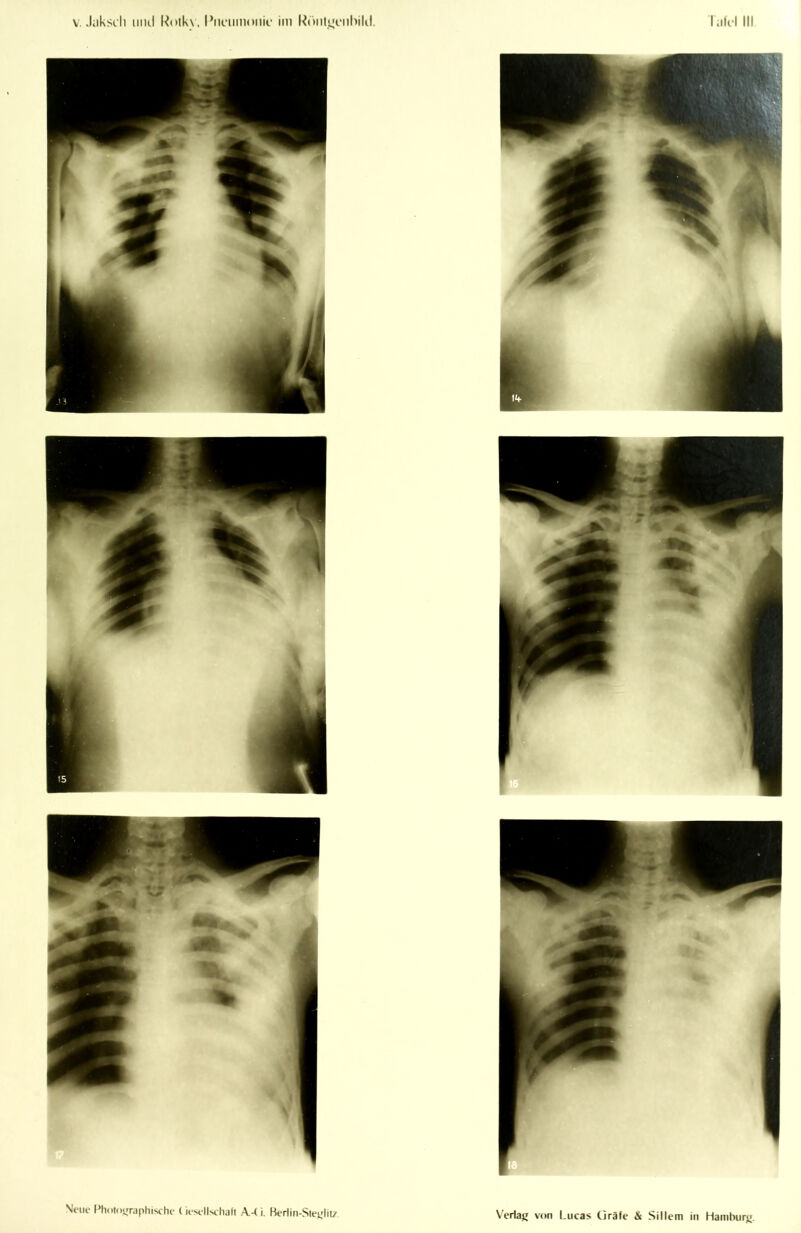

Die Pneumonie im Röntgenbilde ... : mit 59 Röntgenbildern auf 10 Tafeln und 10 Skizzenblättern / von R.v. Jaksch und H. Rotky.

Credit: Die Pneumonie im Röntgenbilde ... : mit 59 Röntgenbildern auf 10 Tafeln und 10 Skizzenblättern / von R.v. Jaksch und H. Rotky. Source: Wellcome Collection.